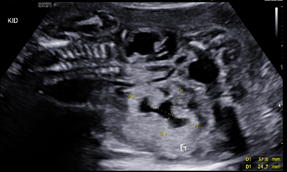

A 25-year-old G2P1001 at 19w2d presented for anatomic ultrasound. Routine prenatal genetic screening indicated an elevated risk for Down syndrome, 1:259. Her prenatal course was otherwise uncomplicated. Initial anatomical evaluation noted adequate amniotic fluid, a markedly distended fetal urinary bladder, moderate-to-marked bilateral renal hydronephrosis, a moderate degree of bilateral hydroureter, and bilateral renal cortical cysts, (Figures 1-4). Patient was sent for second opinion with secondary survey, within 1 week, denoting bladder outlet syndrome with oligohydramnios. A characteristic "keyhole" sign was noted (Figure 5). Patient initially elected for genetic non-invasive prenatal testing and later for genetic amniocentesis, the results of which revealed a normal karyotype/FISH/microarray. At the time of amniocentesis, bladder tap was performed and yielded 160cc of fluid for evaluation of renal function based on urine sodium, chloride, urine osmolality and calcium levels. At 22w3d patient presented for follow up sonographic evaluation; findings revealed significant fetal abdominal ascites, persistent oligohydramnios, a "bell-shaped" chest with only the left lung measurable, and the right lung poorly defined. Bilateral urinary tract dilation was again observed, with the right kidney measuring 2.0 x 3.0cm and the left kidney measuring 2.3 x 1.7cm. The kidneys were echogenic in nature and the parenchyma was thickened up to 7mm, with no pyramids visible. The bladder had severe thickening, measuring up to 7.7mm in diameter. The bladder measured 4.7 x 1.7cm with intraluminal calcifications noted both in the bladder and intestines. The patient was counseled on these new findings and concern for both pulmonary hypoplasia and possible poor renal function. The patient was given the option to proceed with fetal urinary evaluation for renal function and possible bladder shunt vs termination of pregnancy secondary to these findings; she elected for pregnancy termination.1–3

Figure 4 Bilateral renal cortical cysts.

The presence of a posterior urethral valve prevents normal fetal micturition, resulting in bladder distension and subsequent distension of the ureters and kidneys. Diagnostic features of posterior urethral valves on sonography varies, but classically presents in male fetuses with fetal megacystis that may fill the entire abdomen, thickened bladder wall (>3mm) with prominent trabeculae, oligohydramnios, and bilateral hydronephrosis with hypoechoic renal parenchyma and/or cortical cysts that can indicate renal dysplasia. The best diagnostic clue is the presence of a dilated posterior urethra (“keyhole” sign) . While not always seen, its presence, suggests the diagnosis of PUV. These findings however, may be found in other urinary tract conditions. Megacystis is defined as a longitudinal bladder diameter (LBD) > 7mm in the first trimester. However, after the first trimester, it is most commonly defined as failure of bladder emptying during a 45min period of ultrasound examination.5